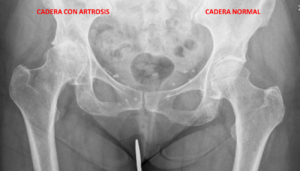

La prueba más útil y empleada para el diagnóstico es la radiografía simple, donde podremos ver si la articulación se encuentra lesionada y cual es el grado de afectación. Pruebas como la resonancia magnética se usan muy ocasionalmente, en casos que queramos descartar otras lesiones.